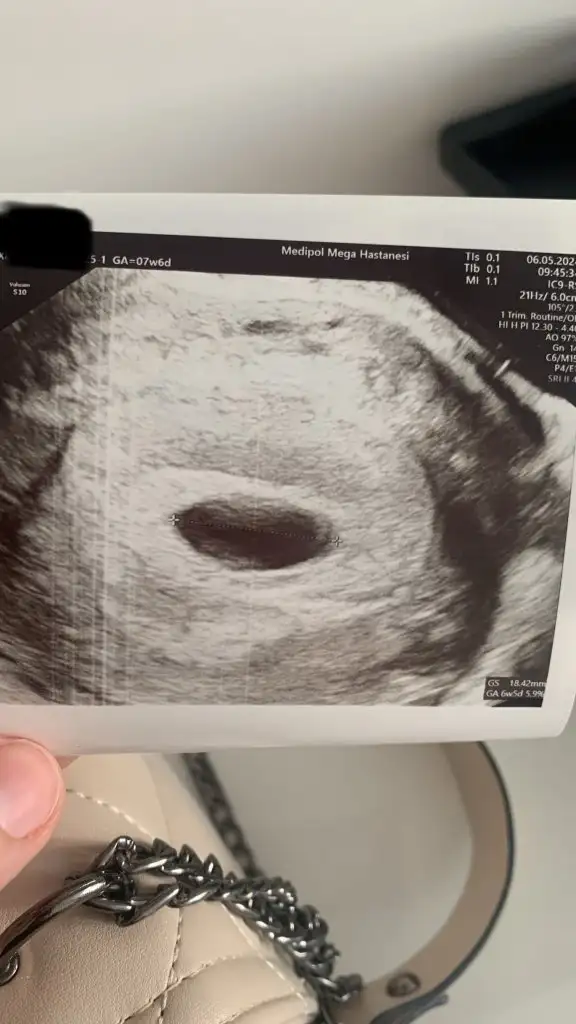

Merhaba benimde böyle görsel ekliyorum bana yorum yapar mısınız? Ben 6+5 görünüyorum. Ama geç döllenme olabilir bilemiyorum kese boyutu 18.42 mm . Ama içinde bebek görünmedi. 1 hafta bekle aç gel eğer bebeği göremezsek alıcaz dedi. Fikir olsun bana nolur yazın…Benim kesemde boyle bende medicanada yaptirdim ultrason 6+2 yolk sactan bahsetti mi sende ben yolk sac bile yok dedigimde birazcik kizdi internetten bakip geliyosunuz bu gebelik bos degil dedi haftaya hepsi gorunur dedi

Canım kese boyutu iyi gibi ama tabi doktor ne derse o bu haftalarda biraz geri olabiliyormuş ya başka Bi doktora daha gidin bence bugün ben iki doktora gittim birincisi kese küçük kalp atışı zayıf düşük riski var dedi içim rahat etmedi daha sonra tekrar ilk gittiğim doktora gttim olumsuz hiçbişey demedi bu daha tecrübeli bir doktor

Canım karından mı bakıldı belki ondan görememiştir vajina daha net her şey ben ilk kesemi vajinadan muayeneyle gördüm içindeki yolk keseside öyle gözükmüştü

İki görüntü karın büyük görsel vajinadan .Canım karından mı bakıldı belki ondan görememiştir vajina daha net her şey ben ilk kesemi vajinadan muayeneyle gördüm içindeki yolk keseside öyle gözükmüştü